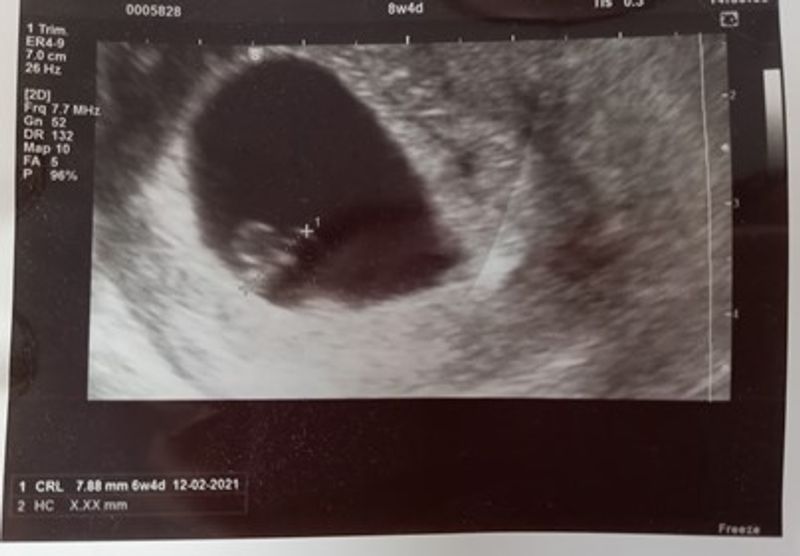

Toen mijn zoon twee jaar was, begonnen de twijfels te komen. “Wil ik opnieuw zwanger worden. Wil ik weer een bevalling meemaken?”, vroeg ik me af. Ik vond zwanger zijn immers niet leuk. Ik voelde mij erg kwetsbaar en labiel. Tevens was mijn bevalling ook geen pretje en had ik een heftige kraamweek. “Wil ik dit echt nog een keer beleven?” Ook speelde de gezondheidsproblemen van mijn zoon mee. Wat brengt dit een hoop stress en zorgen met zich mee voor een ouder. En je hebt natuurlijk geen garantie dat een tweede gezond is. Ik vroeg mij dan ook af of we het wel aankonden, een tweede kind.